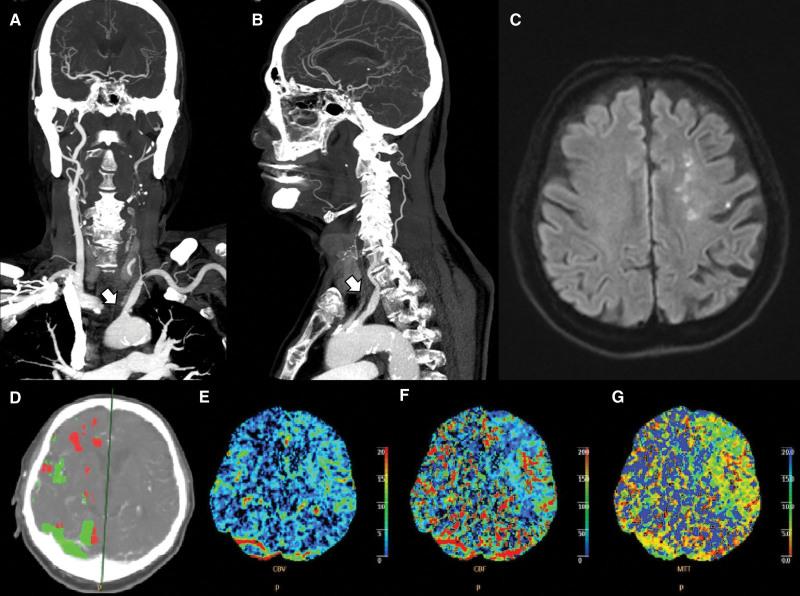

Collateral circulation sustains cerebral perfusion in patients with arterial occlusion. Extensive arterial occlusion may redirect cerebral blood flow to compensate for insufficient perfusion. Cerebral artery occlusion can be observed in computed tomography perfusion imaging with increased mean transit time (MTT). However, in some cases, MTT delay occurs contralateral to the site of stenosis or occlusion. This delay cannot be explained simply by the collateral blood supply. Therefore, the authors considered the similarity of the perfusion delay observed at the normal site to that observed in subclavian steal syndrome.

Three patients were reviewed: the first had severe stenosis in the left proximal internal carotid artery (ICA), and the second had left common carotid artery occlusion and diffusion restriction of the ICA-middle carotid artery border zone. The third patient had total occlusion of the left common carotid artery and right proximal ICA, with multifocal infarctions in the right frontal, occipital, left frontal, and parietal lobes. All 3 patients had a contralateral MTT delay on perfusion imaging.

The site of stenosis or occlusion did not correlate with ipsilateral perfusion delay in these 3 cases. Based on the precedent relationship between infarction and perfusion delay, we developed 2 hypotheses to explain why perfusion decreases on the contralateral side of the occlusion or stenosis. However, this study was limited because we could not identify events, like volume loss or decreased blood pressure, before stroke development.